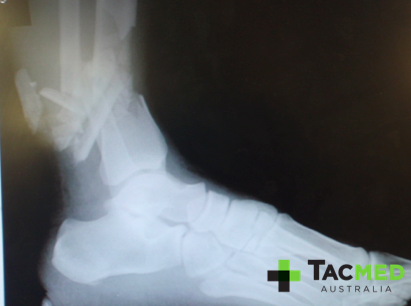

Tertiary blast injury results from casualties being thrown by, or having limbs flail in the blast wind, and may affect any body part. Tertiary blast injuries can include fractures, traumatic amputations, and closed and open brain injuries. When casualties are thrown by the blast wind and strike a wall or other object, the injury profile caused is typically blunt trauma and often results in fractures. Another form of tertiary blast injury is seen in vehicle IED strikes, where instead of the casualty being thrown, the floor of the vehicle is in effect thrown into the feet of the casualties. The result is once again blunt trauma injuries, often involving severe lower limb fractures of restrained passengers, and potential spinal injuries of unrestrained and standing passengers (such as in turrets of armoured vehicles) as they are either propelled into the roof of the vehicle, or ejected from it completely.

The traumatic amputations resulting from tertiary blast injury differ from those caused by secondary blast injury in that, instead of the tissue being shredded away by the shotgun effect of the shrapnel, the limbs are actually torn off by the blast wave. This often results in the disarticulation of the limb through a joint, such as pictured below. Naturally this is purely academic for the first-responder, and the immediate management remains the same, that being placement of a timely arterial tourniquet.